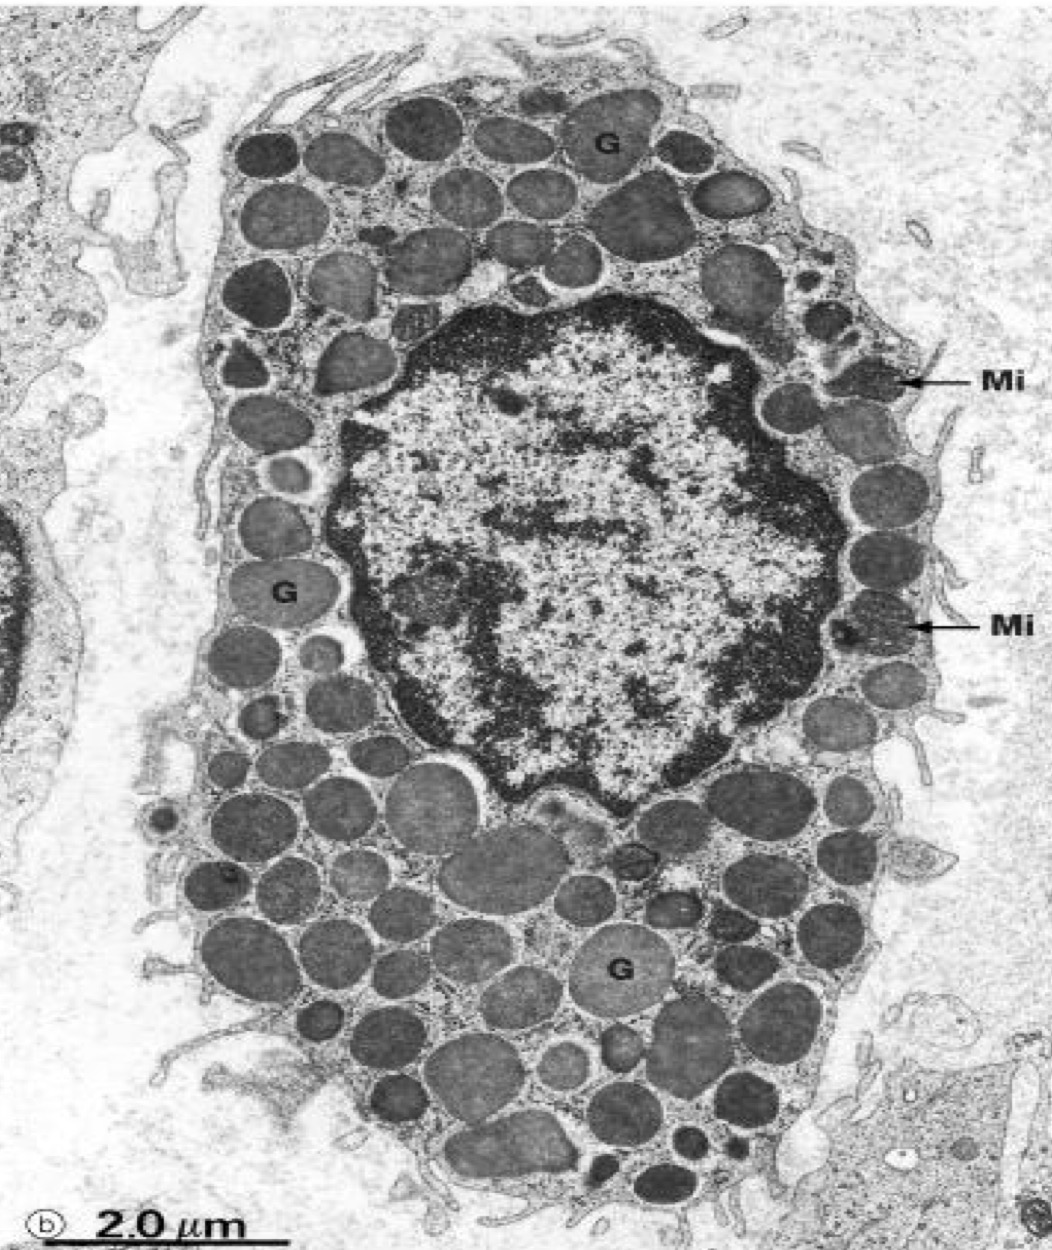

A- identify

B- Histological features

C- Function

A- plasma cell

B-Origin: B Lymphocyte

Cell shape: oval

Nucleus: oval eccentric contain chromatin with cart wheel appearance

Cytoplasm: basophilic due to excessive RER ,Have pale area called negative Golgi images Contain acidophilic

Russel bodies

C-Produce immunoglobulin